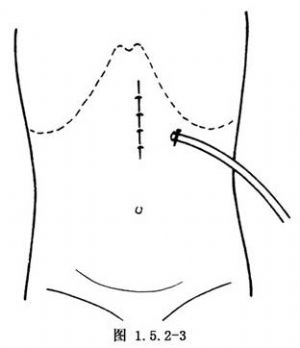

这是最简便的一种暂时性胃造口术。取平卧位,做上腹部中线或左上腹直肌切口。进入腹腔后,将胃体部置于手术野中,一般选择在胃体部前壁胃大弯小弯的中点处造口。用湿纱布垫覆盖于手术野四周,保护腹腔防止污染。用细的不吸收线于预定造口处做一荷包缝合。于荷包缝合的中央切开胃壁全层,切口大小以正好置入导管为度。用F14~16号导尿管或乳胶管经此切口插入胃腔3~5cm,亦可用蕈状导管或带气囊的导管插入,以防脱出。收紧结扎荷包缝合线使浆膜内翻紧贴导管。于第1个荷包缝合线外1~1.5cm处再做一荷包缝合并收紧结扎。必要时可做第3层荷包缝合(图1.5.2-1)。于切口左侧腹壁戳一小口,将导管经此口拖出。造口周围的胃壁与腹壁戳口四周的腹膜固定缝合3或4针,应无张力(图1.5.2-2)。最后将导管固定缝合于皮肤,按层缝合切口(图1.5.2-3)。